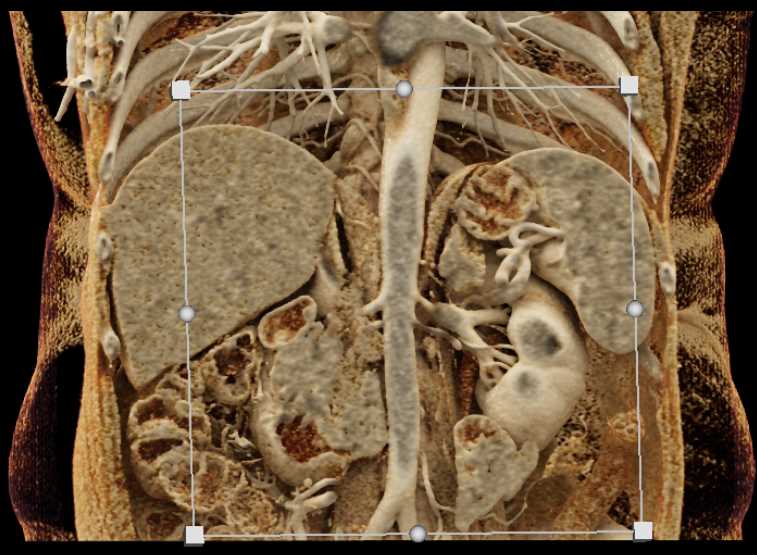

Small Bowel Carcinoma with Carcinomatosis